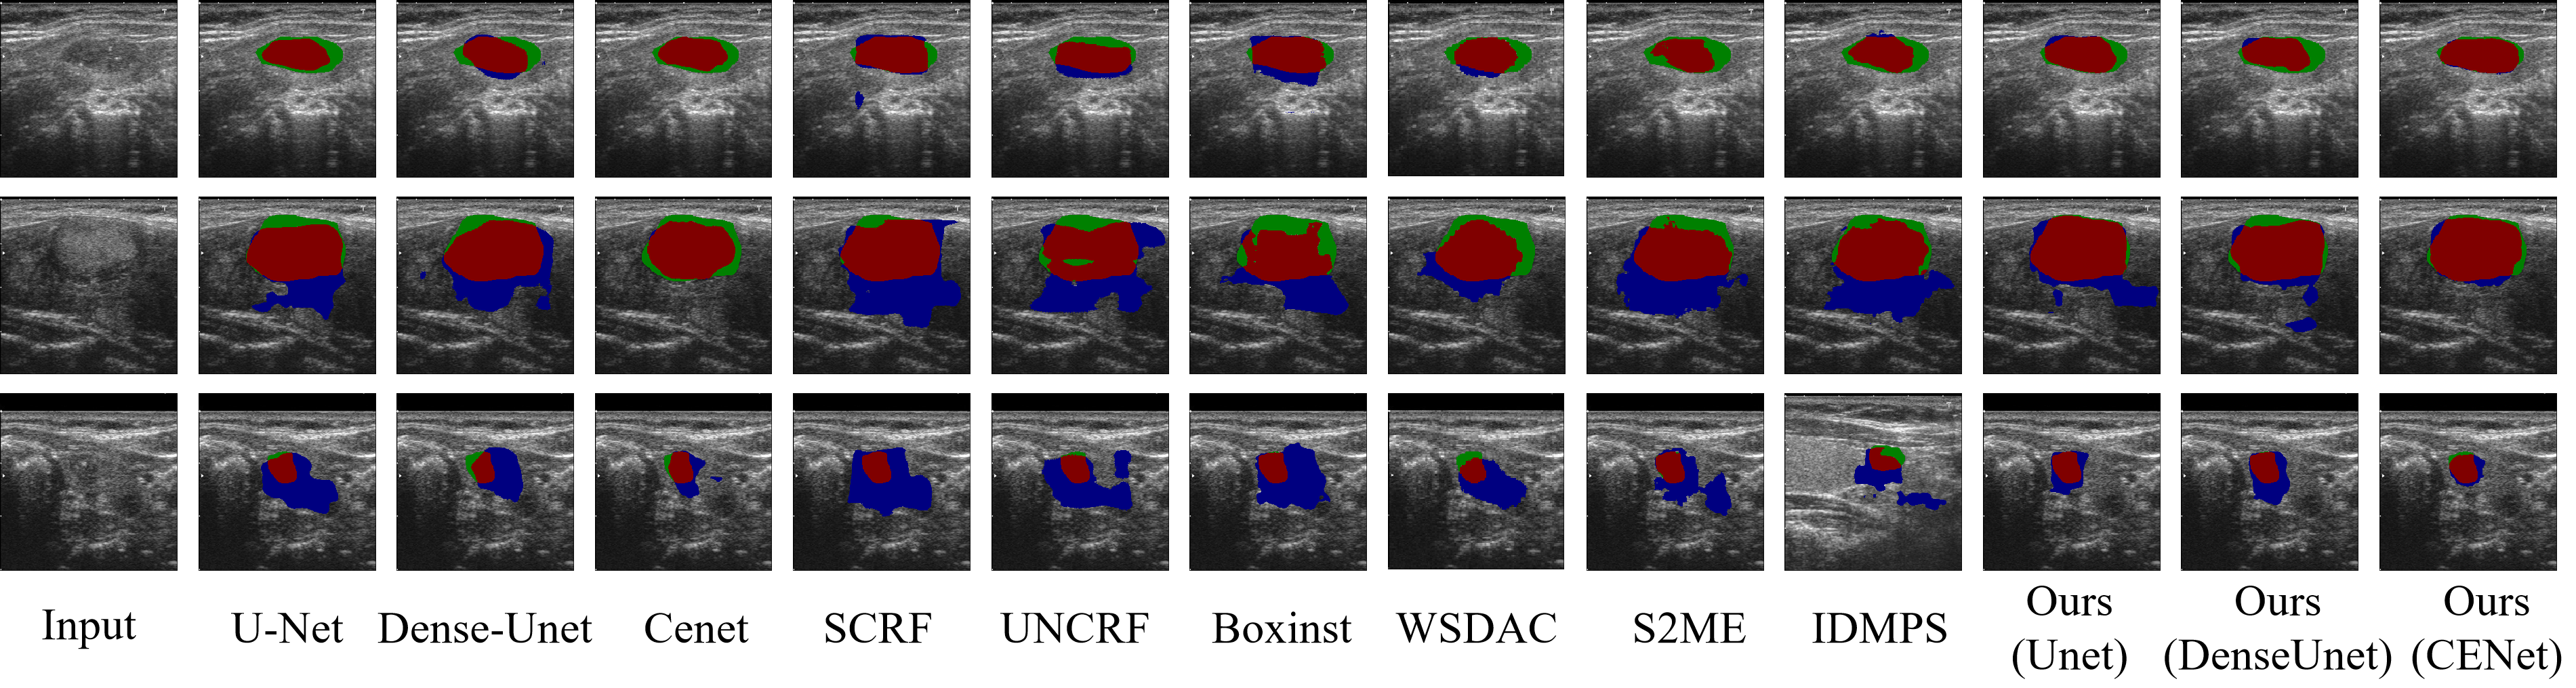

The segmentation performance of our proposed method was compared against the state-of-art weakly supervised methods SCRF[14], UNCRF[15], BoxInst[16], WSDAC[20], S2ME[22], IDMPS[21], and fully supervised methods U-Net[8], Dense-UNet[9] and Cenet[12]. The quantitative results of TN3K and DDTI are shown in Table. 2. The qualitative results of TN3K and DDTI are shown in Fig. 3 and Fig.4, respectively.

Refer to caption

Figure 3: Quantitative comparison results on TN3K dataset. Red indicates correct thyroid predictions, green represents missing thyroid segmentation, and blue shows an overestimation of other organs as the thyroid.

As shown in Fig. 3, SCRF and UNCRF tended to produce box-like segmentation with significant over-segmentation. WSDAC and S2ME frequently under-segmented thyroid nodules in images with multiple nodules or irregular nodule shapes. While BoxInst and IDMPS outperformed other existing methods in high-contrast scenarios, such as the example in the third row, they still struggled with under-segmentation of incomplete nodules located at image boundaries. In contrast, our proposed method achieved more consistent segmentation regions and delicate segmentation edges, while exhibiting even less over- and under-segmentation than fully supervised networks using the same backbone. Quantitative results in Table 2 further support that our framework using the U-Net backbone outperformed state-of-the-art weakly-supervised methods. Specifically, it achieved an average mIOU of 69.30%, a Hausdorff distance (HD) of 5.01 mm, a DSC of 79.10%, and a precision (Pr) of 80.64%. These results were even better than the fully supervised U-Net, which achieved 64.76% mIOU, 5.83 mm HD, 75.13% DSC, and 77.66% Pr.

Figure 4: Quantitative comparison results on DDTI dataset. Red indicates correct thyroid predictions, green represents missing thyroid segmentation, and blue shows an overestimation of other organs as the thyroid.

As illustrated in Fig. 4, fully supervised networks exhibited substantial over-segmentation in images where the foreground and background tissues are similar. Weakly supervised algorithms, such as SCRF, UNCRF, and S2ME, struggled with severe over-segmentation of small targets, as well as in images with similar foreground and background tissues. Both BoxInst and WSDAC encountered significant challenges with over- and under-segmentation when processing such images. Notably, BoxInst delivered superior segmentation results with minimal over-segmentation in simpler background scenarios, while WSDAC tended to exhibit more under-segmentation in these cases. IDMPS outperformed other weakly supervised algorithms by reducing over-segmentation in small nodules, however, it still faced substantial issues with under-segmentation and excessive over-segmentation in more complex cases. In contrast, our algorithm not only reduced over-segmentation but also illustrated enhanced shape adaptation, surpassing fully supervised methods. Additionally, by incorporating a more efficient feature extraction backbone such as CENet, we achieved better segmentation precision, with accurate shape delineation and fine edge fitting. The quantitative comparison presented in Table 2 further substantiates these qualitative observations.